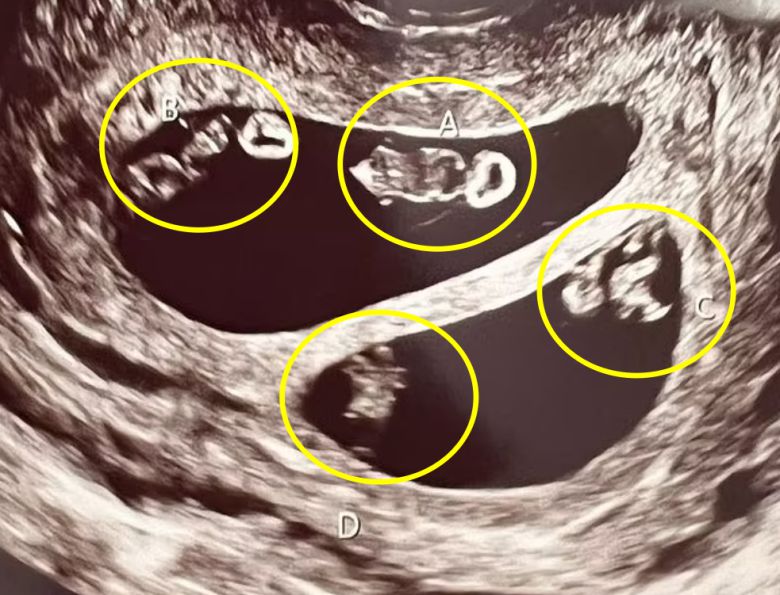

7000만 분의 1 확률로 두 쌍의 일란성 쌍둥이를 동시 임신한 여성(왼쪽)의 초음파 영상 캡쳐(오른쪽) |

임신이라는 사실을 직감한 뒤 병원을 찾았을 때, 초음파 검사를 하던 담당 의사는 의아함에 고개를 갸우뚱거렸다. 그녀의 자궁 안에서 총 4명의 태아가 자라고 있으며, 이는 네 쌍둥이가 아닌 일란성 쌍둥이 2쌍으로 추정됐기 때문이다.

7000만 분의 1 확률로 두 쌍의 일란성 쌍둥이를 동시 임신한 여성의 초음파 영상 캡쳐 |

네스의 자궁에서 자라는 일란성 쌍둥이는 남자아이 2명, 여자아이 2명으로 확인됐다.

담당 의사는 “네 쌍둥이가 아닌 일란성 쌍둥이 두 쌍을 동시에 임신하는 경우는 처음 봤다. 당초 초음파 검사를 통해 이를 확인했을 때, 이런 ‘현상’이 가능한 지 알수가 없어서 곧바로 관련 자료를 찾아봐야했다”고 전했다.

뉴욕포스트는 전문가를 인용해 “자연 임신을 통해 네 쌍둥이를 임신할 확률은 70만 분의 1~100만 분의 1로 극히 희박하다. 여기에 두 쌍의 일란성 쌍둥이를 동시에 임신할 확률은 7000만 분의 1에 달한다”고 전했다.